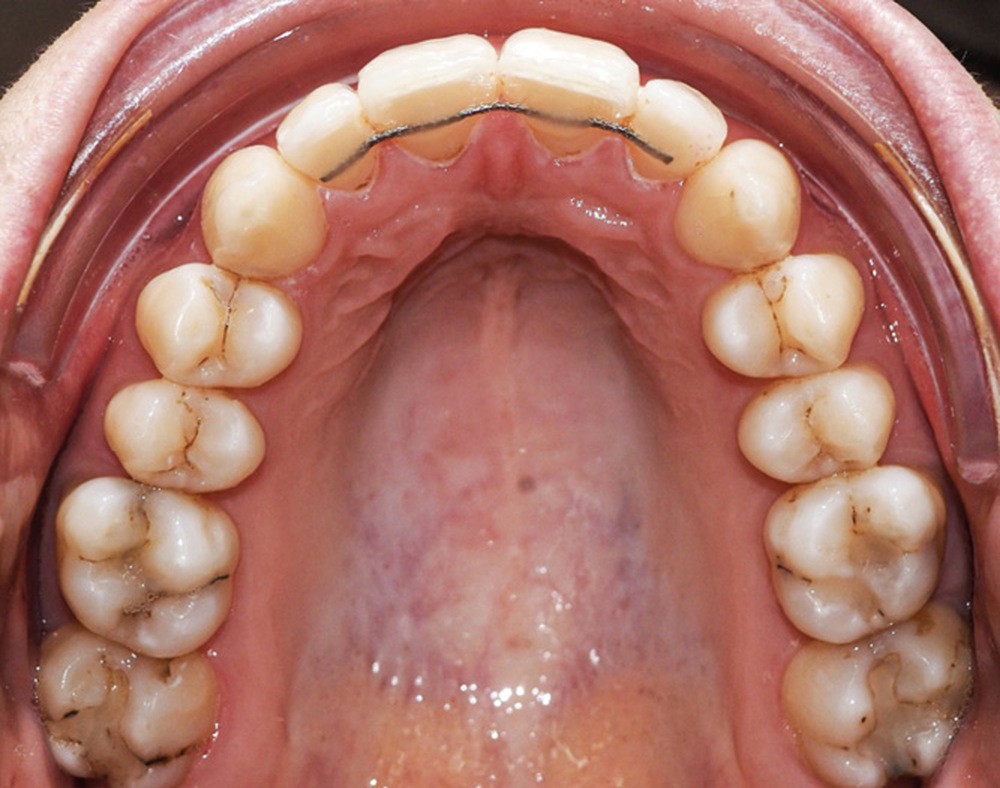

Examen endo-buccal (fig. 2a-e)

L’arcade maxillaire est parabolique, la 12 présente une légère mésio-rotation. L’arcade mandibulaire est également parabolique avec un encombrement antérieur estimé à 6 mm. On note une dyschromie de la 31, dont le test de vitalité est négatif. Le parodonte est fin.

Les incisives maxillaires sont de forme triangulaire [1] et l’indice de Bolton est de 97 % qui traduit la présence d’une DDD par excès mandibulaire.

Le choix final s’est donc porté sur l’extraction de la 31 avec stripping maxillaire. Ce stripping avait deux objectifs : corriger la DDD créée par l’extraction de 31 (indice de Bolton de 90,8 % post extraction, soit une DDD par excès maxillaire) et éviter l’apparition de triangles noirs entre les incisives maxillaires liée à leur forme triangulaire [1]. Le set-up réalisé en début de traitement lingual est un avantage car il permet de prévisualiser la correction de la DDD créée et la quantité de stripping nécessaire.